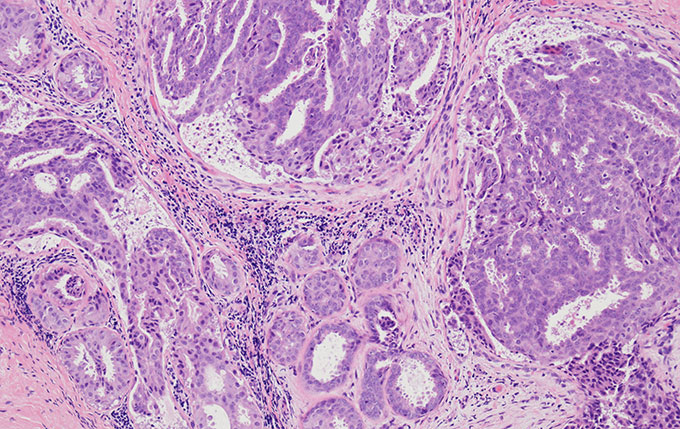

明场

明场聚光镜支持4×至100×成像,并且可以与CX-AL附件透镜配套使用,阻挡杂散光,在整个倍率范围内提供明亮的柯勒照明。